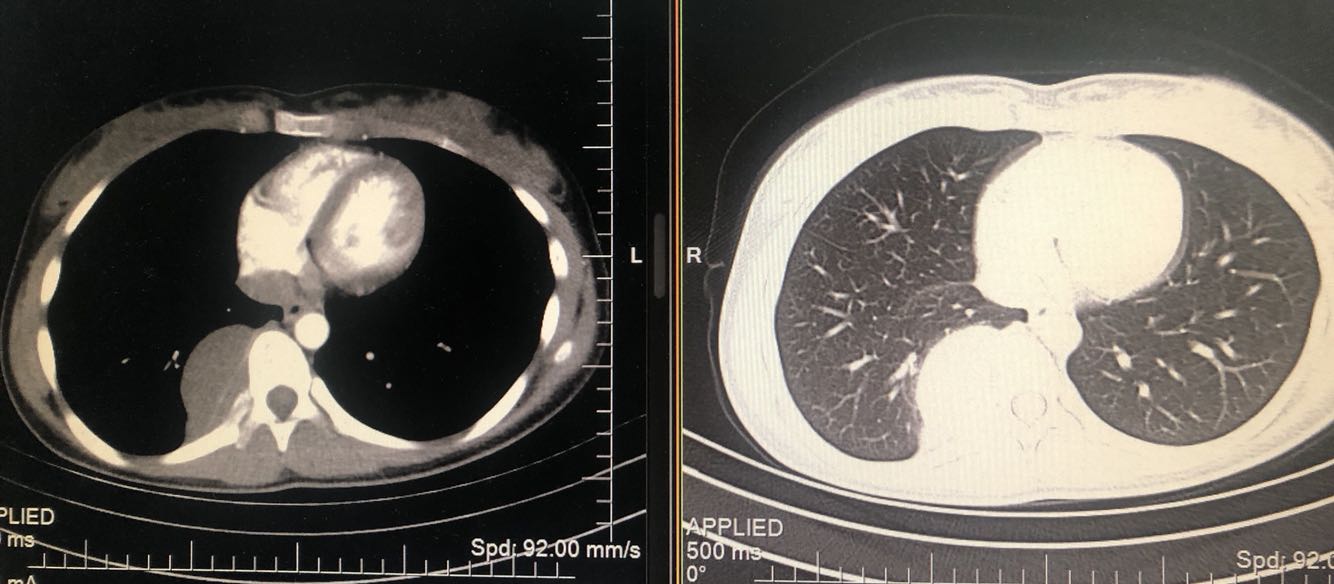

纵膈旁软组织团块性质待定

查体:浅表淋巴结不大,双肺叩清音,双肺呼吸音清,未闻及干湿性啰音。心腹查体未见异常。 既往史:体健,否认药物过敏史。 辅助检查:肺CT示后下纵膈脊柱旁软组织密度影,边界清楚。

肺穿刺活检组织病理:神经纤维组织

诊断:纵膈神经纤维瘤 治疗:胸外科手术,全麻下行胸腔镜辅助右侧纵膈肿物切除术。术后病理:符合神经纤维瘤。